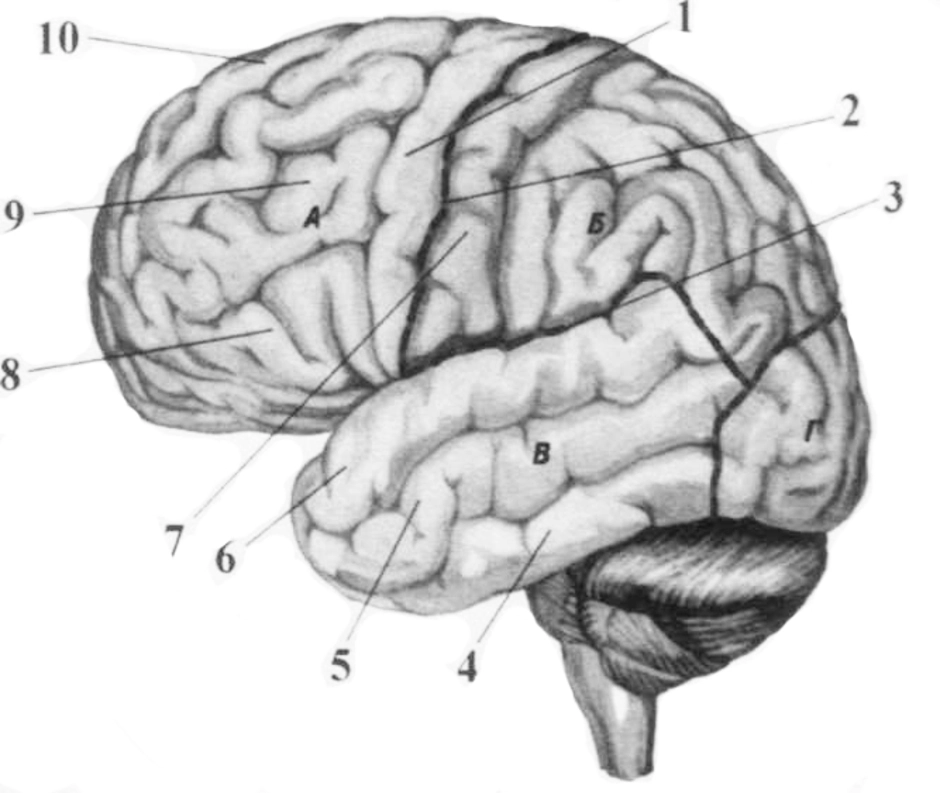

Анатомические снимки верхнелатеральной поверхности головного мозга